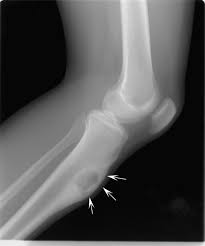

Bone cancer can affect any bone, but most cases develop in the long bones of the legs or upper arms. Ask your doctor about your bone cancer, including your treatment options and, if you like, your prognosis. The affected leg or joint develops pain that is often described as consistent and dull, like a persistent ache. Sometimes bone cancer makes a sudden appearance as a lump in the leg, or in worst case scenario, as a pathologic fracture. Is felt at and around the site of the metastasis

Besides a deep or dull aching pain that is worse at night and during activity, swelling around the bone, weight loss, and fatigue may occur with bone cancer. This variety of bone cancer occurs most often in children and young adults, in the bones of the leg or arm. Bone tumors happen more often in people who've had radiation, stem cell transplants. This is called referred pain. The cancer has grown into the major nerves and blood vessels around your bone tumour you developed an infection after your limb sparing surgery that meant the false bone had to be removed the position of the tumour means that limb sparing surgery is not technically possible In this tumor, the cancerous cells produce bone. If you feel a deep ache in your bone that doesn't go away, you may have bone cancer and you should go directly to bone cancer centers. Sometimes bone cancer makes a sudden appearance as a lump in the leg, or in worst case scenario, as a pathologic fracture. You might have pain or tenderness most of the time, even when you're resting. Is felt at and around the site of the metastasis The bone pain is described as aching, throbbing, stabbing, and excruciating.this can lead to insomnia, loss of appetite, and inability to carry out normal daily activities. As you learn more about bone cancer, you may become more confident in making treatment decisions. Previously, fall of 2018 i had neck cancer.

Bone tumors happen more often in people who've had radiation, stem cell transplants. Pain is the most common symptom of bone cancer. In some cases, the pain is a result of cancer therapy, such as chemotherapy or radiotherapy. If a bone with a tumor breaks, or fractures, in a leg, it can lead to a pronounced limp. Bone pain can cause a dull or deep ache in a bone or bone region (e.g., back, pelvis, legs, ribs, arms).